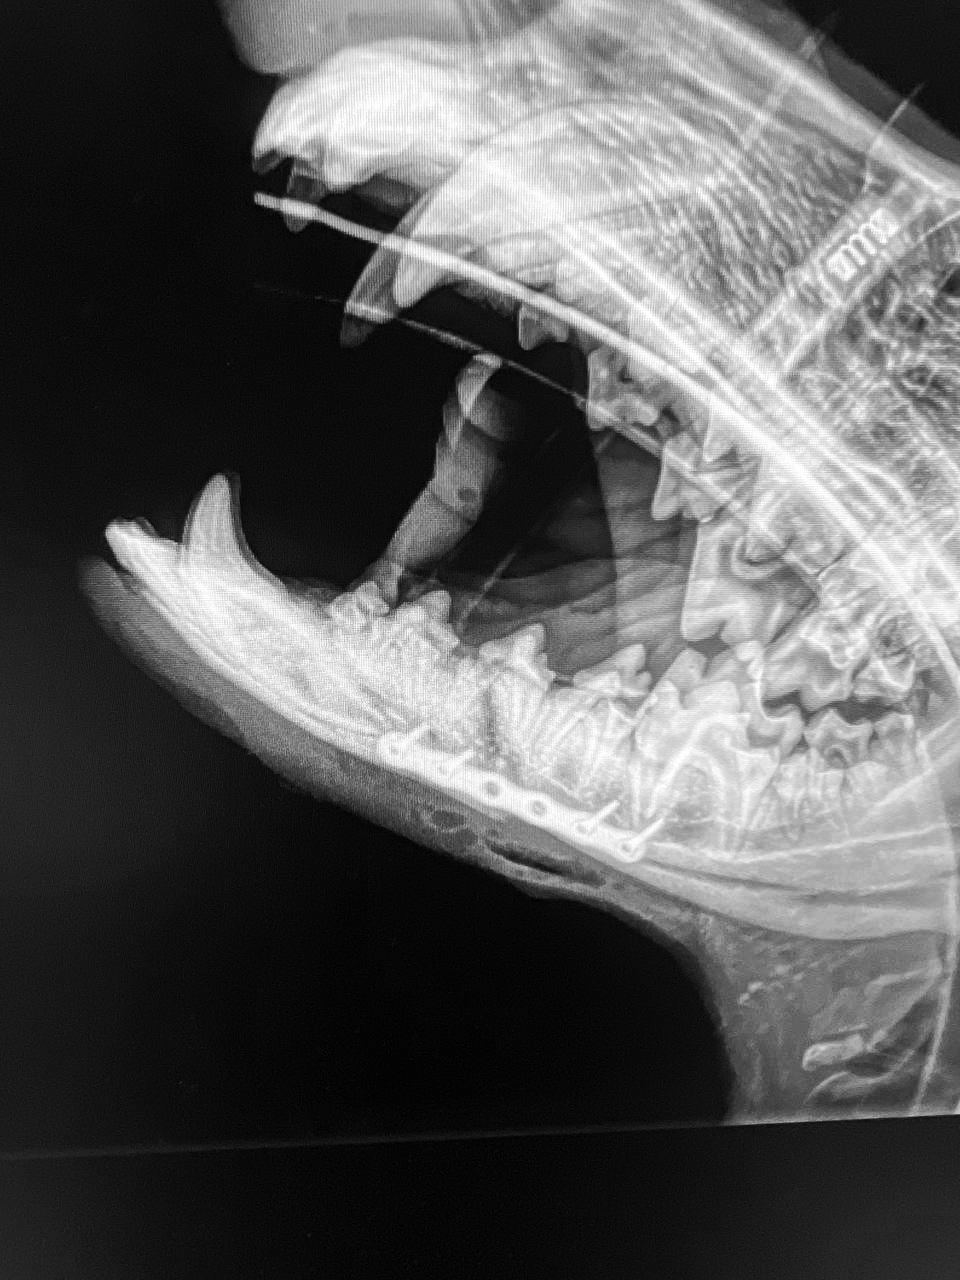

X-Ray Image courtesy of Dr. Ilya Zhuravchak.

Case Spotlight: Dr. Ilya Zhuravchak’s Success with a Lower Jaw Fracture

Dr. Ilya Zhuravchak recently showcased the precision and effectiveness of the LeiLOX 1.5 mm titanium lightweight locking plate in treating a challenging lower jaw fracture. The patient, a small animal with a delicate mandibular structure, required a solution that offered both strength and minimal weight to avoid additional stress on the already fragile bone.

Using the LeiLOX system, Dr. Zhuravchak achieved a stable and anatomically precise fixation, allowing for optimal healing conditions. The lightweight titanium plate not only provided the necessary durability but also ensured biocompatibility, reducing the risk of complications and promoting faster recovery.

This case highlights the versatility and innovation of the LeiLOX system, proving its capability to handle even the most intricate and demanding fracture repairs with confidence.